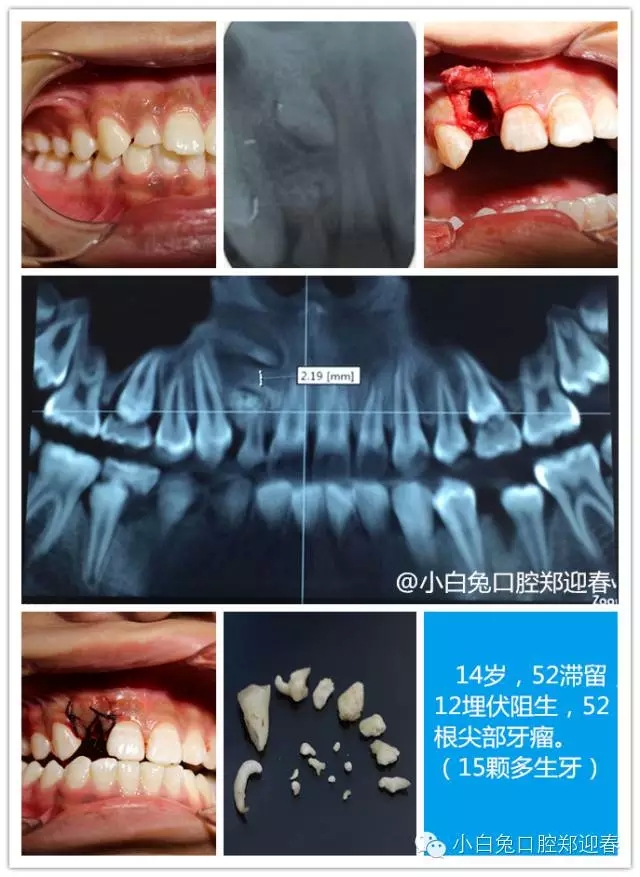

“多生牙”案例集錦(鄭穎春)......

額外牙可發(fā)生于乳牙列,也可發(fā)生于恒牙列,但恒牙列發(fā)生率多于乳牙列。額外牙經(jīng)常在上頜出現(xiàn),上、下頜出現(xiàn)比例為10∶1,可單個或多個、單側(cè)或雙側(cè)出現(xiàn),形態(tài)可同正常牙,也可是畸形牙、過小牙。